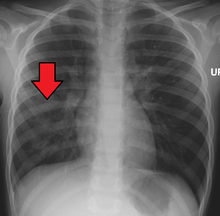

A chest X-ray showing a very prominent wedge-shape area of airspace consolidation in the right lung characteristic of bacterial pneumonia. | |

A chest radiograph is frequently used in diagnosis.[19] In people with mild disease, imaging is needed only in those with potential complications, those not having improved with treatment, or those in which the cause is uncertain.[19][48] If a person is sufficiently sick to require hospitalization, a chest radiograph is recommended.[48] Findings do not always match the severity of disease and do not reliably separate between bacterial infection and viral infection.[19]

X-ray presentations of pneumonia may be classified as lobar pneumonia, bronchopneumonia (also known as lobular pneumonia), and interstitial pneumonia.[51] Bacterial, community-acquired pneumonia classically show lung consolidation of one lung segmental lobe, which is known as lobar pneumonia.[29] However, findings may vary, and other patterns are common in other types of pneumonia.[29] Aspiration pneumonia may present with bilateral opacities primarily in the bases of the lungs and on the right side.[29] Radiographs of viral pneumonia may appear normal, appear hyper-inflated, have bilateral patchy areas, or present similar to bacterial pneumonia with lobar consolidation.[29] Radiologic findings may not be present in the early stages of the disease, especially in the presence of dehydration, or may be difficult to be interpreted in the obese or those with a history of lung disease.[20] A CT scan can give additional information in indeterminate cases.[29]